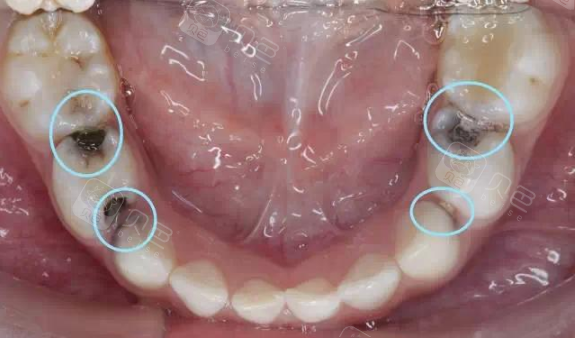

图片尺寸1920x1080![远中面e.咬合面e[解析] 龋损.](https://imgs.wantubizhi.com/img/ADDA3C5D760C6828B77B505A29D43E83FE5803CEA07A6AC9CD53C6C8AA528E9FE3DECF6527942F21B1CC7D3C8D2B1C4B010F0E977916A3E157DAEF5CC09E79CB53D1E4B6A8398E9F781BDE716133C57A2A5C80E13A063AA3763F18A7C8495CFF)

远中面e.咬合面e[解析] 龋损.